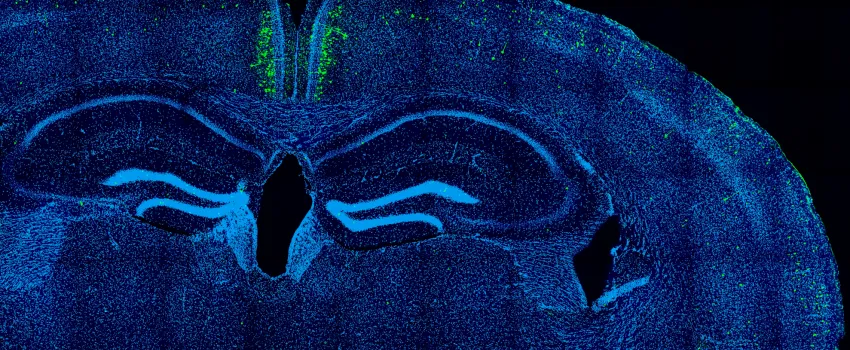

13 Feb 2025 Scientists use deep learning to compare gene regulation in different cell types of human and chicken brains Member news